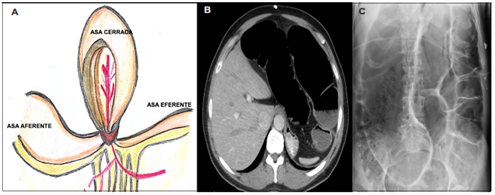

Por eso, es necesario reconocer oportunamente una obstrucción intestinal en asa cerrada y considerarla una urgencia quirúrgica, debido a las consecuencias derivadas de un eventual retraso en su resolución, pues el riesgo de estrangulación e infarto es alto, con tasas de mortalidad del 10 al 35 % 13. La Figura 1 ilustra una representación esquemática y radiológica de una obstrucción intestinal en asa cerrada.